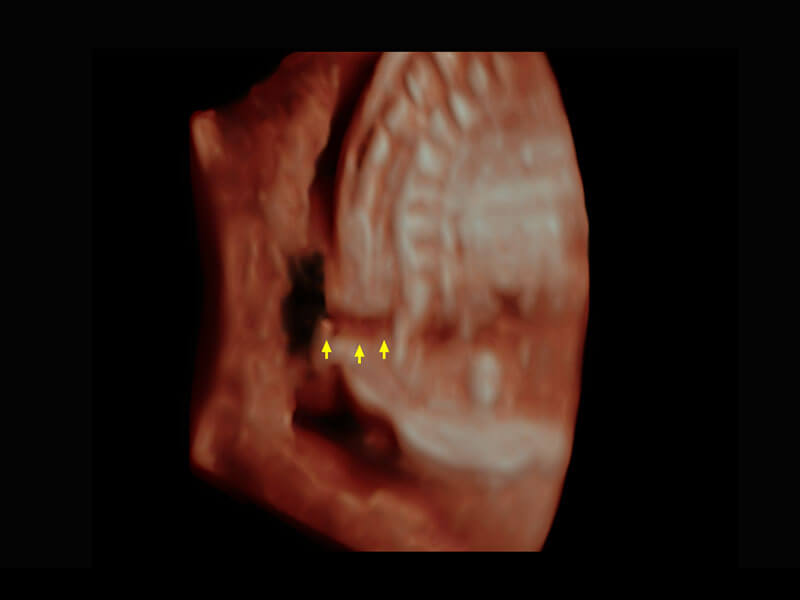

P60为盆底超声检查提供应用方案,多种腔内及腹部容积探头提供从二维、三维到四维的优异图像品质,实时快速三维容积数据获取,专业的测量工具包等人性化设计,为超声医生诊断提供有力保障。

Lev.Hiat A-r: 16.33 cm2

Lev.Hiat H-r: 53.70 mm

Lev.Hiat W-r: 43.96 mm

Lt-LUG-r: 24.16 mm

Rt-LUG-r: 19.94 mm

能够简化盆底检查的操作流程,可在二维模式及三维成像模式下实现一键自动提取出标准切面、自动识别当前切面、自动测量,提升盆底检查的高效性,同时也能让青年医生快捷的获得准确的检查结果。